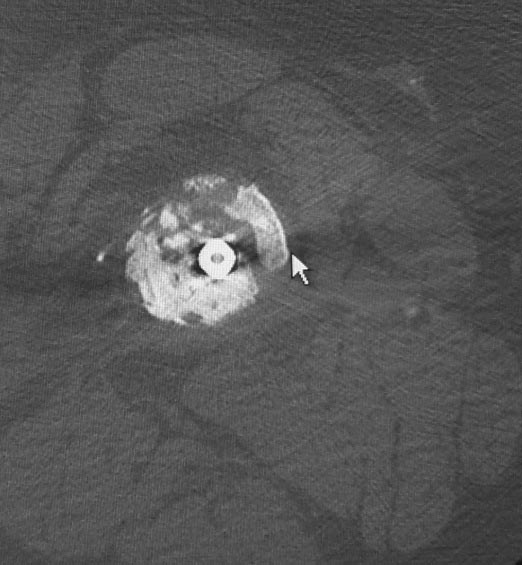

Уважаемые коллеги. Хотелось бы выслушать мнения и советы по представленному случаю. Пациент 42 лет, вес 130 кг, рост около 160 см, сахарный диабет в легкой форме (впервые выявлен после травмы). Травма в феврале 2011 г. - упал с мотоцикла на отдыхе за рубежом. По возвращении в Россию был прооперирован в несколько этапов: в марте 2011 г. - остеосинтез обеих костей правого предплечья пластинами по поводу открытого перелома; интрамедуллярный остеосинтез правого бедра; остеосинтез проксимального конца правой большеберцовой кости. В апреле 2011 г. был доставлен 1 блокирующий винт в дистальное отверстие гвоздя и выполнена пластика крестообразных и наружной боковой связок левого коленного сустава. В феврале 2012 г. были удалены фиксаторы с проксимального конца правой большеберцовой кости и выполнена пластика крестообразных и наружной боковой связок правого коленного сустава. За это время пациент смог начать ходить, сначала с костылями, а затем - без дополнительной опоры. Летом 2013 г. решил укрепить ноги с помощью подъемов пешком на пятый этаж. В результате - усталостная рефрактура правого бедра и перелом интрамедуллярного гвоздя. 09.09.2013 - реостеосинтез латеральным бедренным гвоздем с пластикой костной аутостружкой + СhronoS. Сейчас, через 6 мес после операции, может ходить без дополнительной опоры, периодически беспокоит болезненность в области правого бедра. На сегодняшних КТ - отсутствие признаков консолидации. Нужно ли что то делать и, если да, то что? Рассматриваемые варианты: повторная костная пластика дефекта; доставить блокирующие винты (самый проксимальный винт был удален через 3 мес после операции). Еще раз менять гвоздь не хотелось бы. На представленных снимках: бедро в 2011 г., через несколько мес после операции; в 2012 г., на стадии консолидации; со сломанным гвоздем; сразу после повторной операции (3 рентгенограммы). Все КТ - сегодняшние. Заранее спасибо за ответы.

ждать-не ждать? Срочности нет, подождать можно, но активно, т.е. оценить клиническую и рентгенологическую динамику: два месяца назад, сейчас и еще через пару месяцев. Уменьшатся боли, появится более убедительная мозоль - ждите и наблюдайте дальше. Отсутствие положительной динамики можно приравнять к отрицательной динамике. Очевидно, что здесь имеют место быть обе проблемы: биологическая -мозоль слабая и механическая - тонкий гвоздь, недостаточная стабильность. Тогда -удаление, рассверливание (очень аккуратное, по 0.5 мм шаг, острыми фрезами, чтобы не пожечь кость - кортикал толстый и довольно прочный). Для 130 кг диаметр гвоздя минимум 12 мм, лучше больше. Здесь можно и 14мм гвоздь взять и блокировать дистально винтами 6,0 мм. Открывать перелом и пытаться делать еще пластику экстрамедуллярно не стоит. Рассверливания будет достаточно.

Боли в области ложного сустава подтверждают, что ожидания не помогут и приведут к повторному перелому интрамедуллярного гвоздя. Стандартная процедура - рассверливание и толстый гвоздь в динамике. Нагрузка с первых дней.